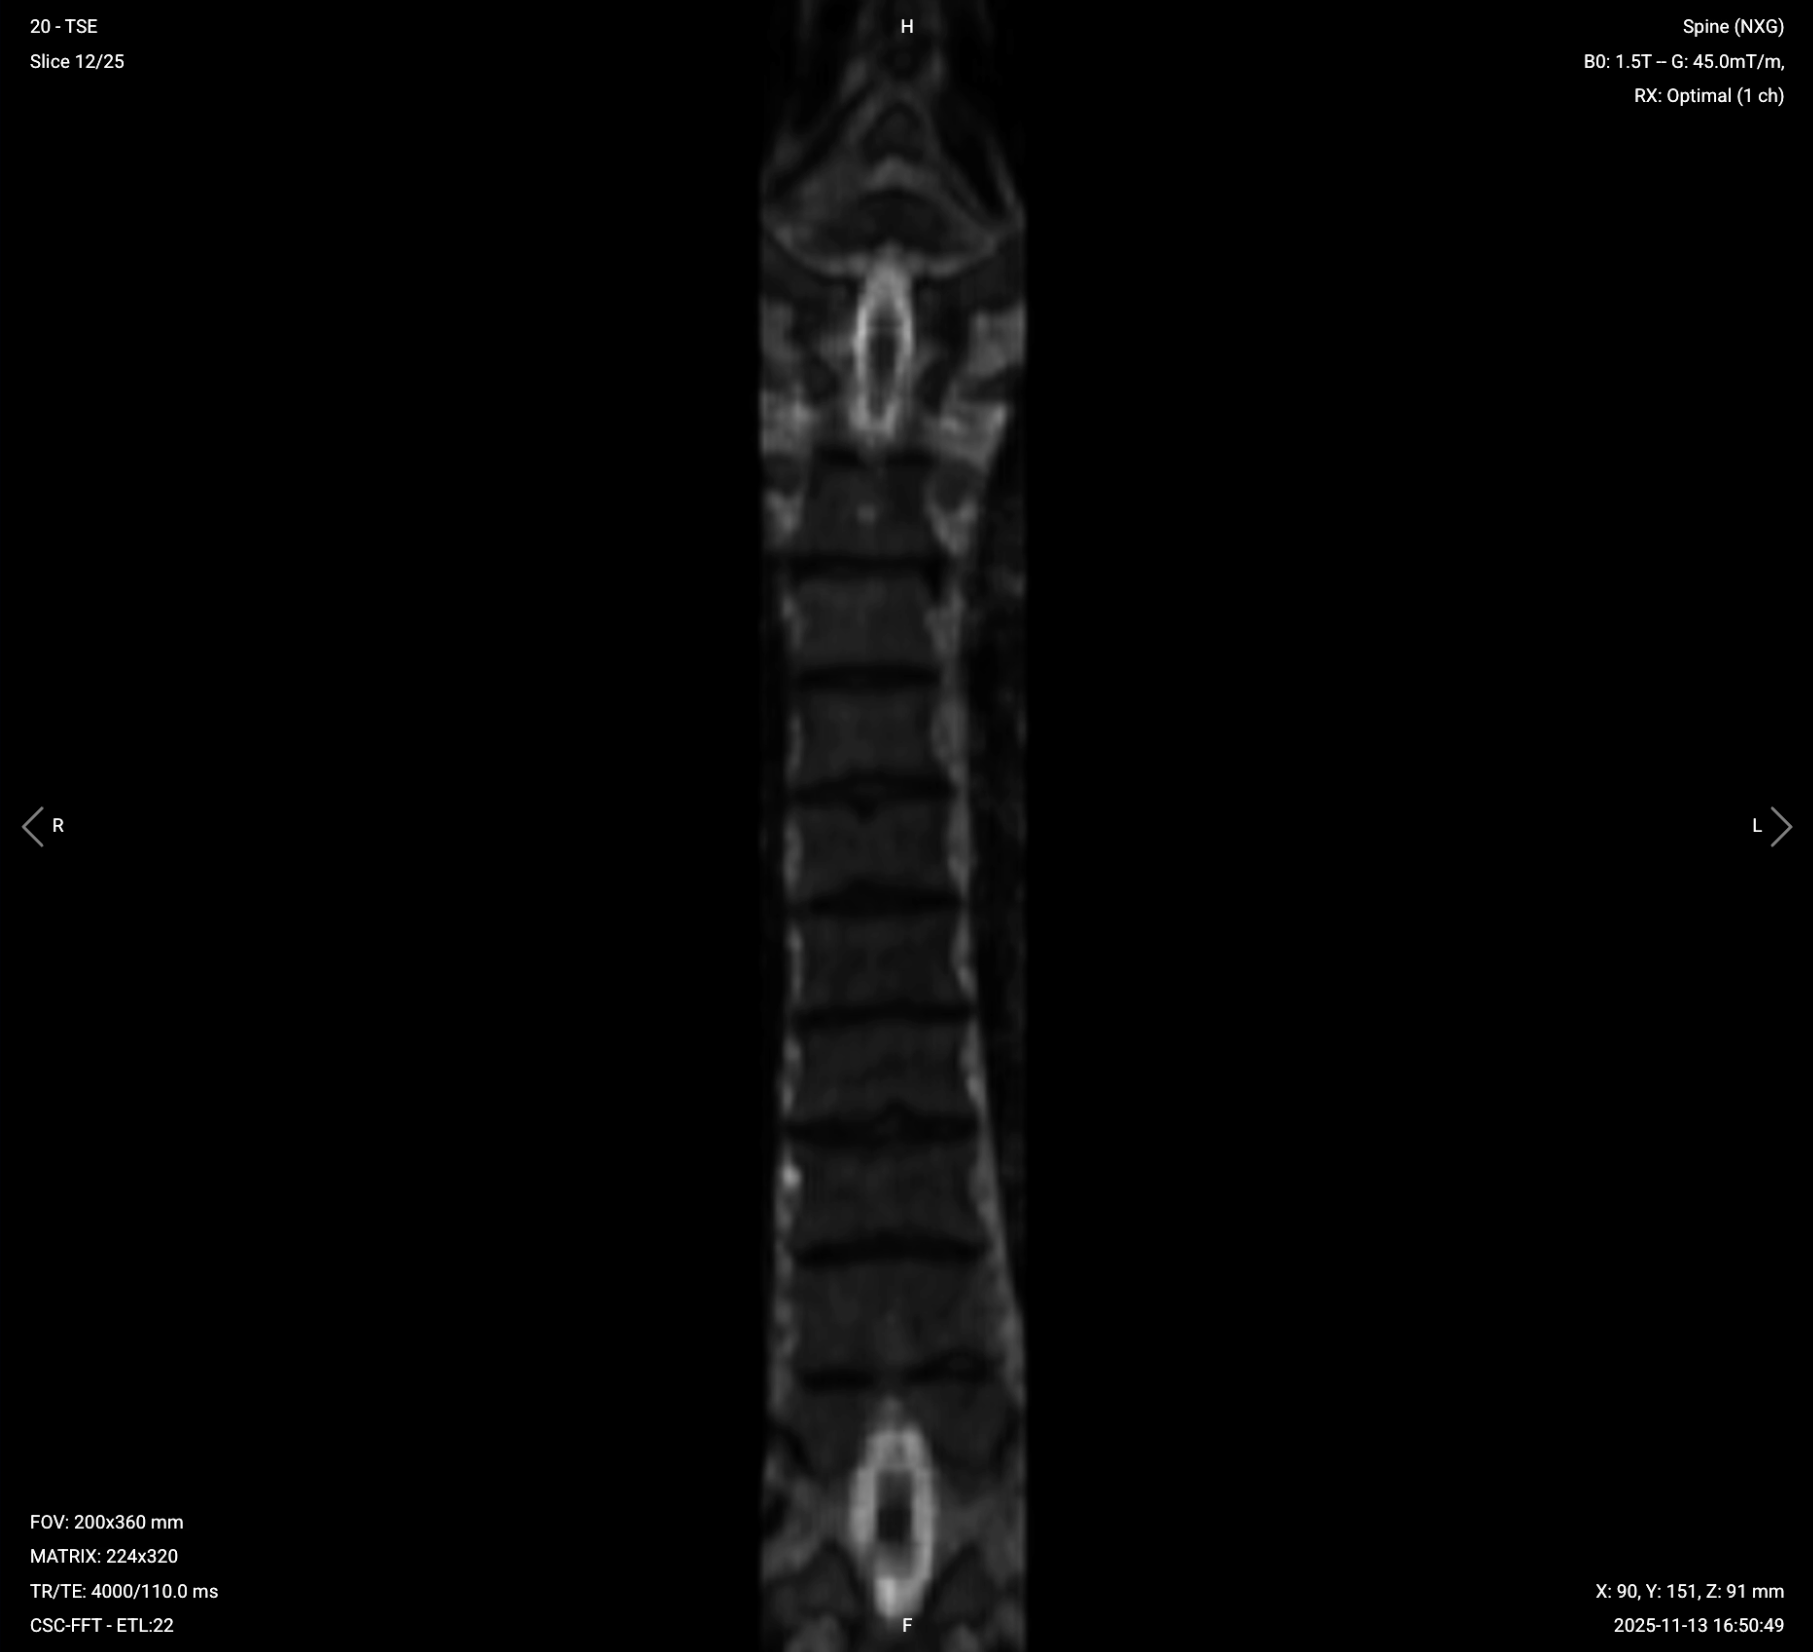

Parameters for Coronal T2 TSE:

| Field-of-View (FOV) | 200 × 360 mm | Rectangular FOV optimized for the thoracic spine's vertical extent, covering superior-to-inferior while minimizing anterior-posterior to reduce scan time. |

| Matrix | 224 × 320 | Medium matrix size to get sufficient resolution and detail while maintaining short scan time and high SNR. |

| Foldover Direction (Phase) | Foot-to-Head (FH) / Superior-to-Inferior | To align with cerebrospinal fluid flow and reduce flow artifacts. |

| Number of Slices | 22–26 | Enough slices to fully cover all 12 thoracic vertebrae. |

| Slice Thickness | 4 mm | Medium thickness to get good resolution without sacrificing scan time or SNR. |

| Slice Gap | 0.4 mm | 10% of slice thickness to prevent crosstalk while ensuring continuity. |

| NEX / Averages | 1–2 | To get enough SNR while keeping scan time short. |

| Turbo Factor / ETL | 16–24 | Higher turbo factor to enhance T2 contrast and reduce scan time. |

| Bandwidth | 50,000 Hz | Medium bandwidth balances SNR with chemical shift artifact reduction. Lower than typical values to improve SNR in the challenging thoracic region. |

| Fold-over Suppression | Yes | To avoid aliasing or wrap-around artifacts. |

✅ Coronal T2 TSE of Thoracic Spine – Correct Image Example:

Things to Look for in Coronal T2: